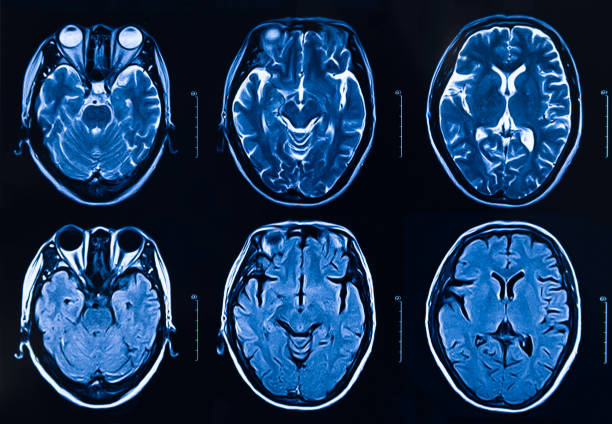

腦出血 (ICH )是一種常見且致命的中風(fēng)亞型,其特征是出血進(jìn)入腦實(shí)質(zhì)并可能進(jìn)入腦室。ICH只占所有中風(fēng)的10-15%左右,但卻是最致命的亞型之一,不到50%的受影響患者在中風(fēng)后存活1年。ICH也不成比例地影響黑人和亞裔美國人。

腦出血的主要危險(xiǎn)因素包括吸煙、大量飲酒和高血壓。神經(jīng)系統(tǒng)惡化最初是由血腫擴(kuò)張和占位效應(yīng)介導(dǎo)的,伴隨著功能性神經(jīng)組織的破壞和顱內(nèi)壓(ICP)的增加。此外,水腫、氧化應(yīng)激、伴有全身炎癥的神經(jīng)炎癥、局部小膠質(zhì)細(xì)胞激活和血腦屏障滲漏通常存在于ICH部位或周圍組織中。